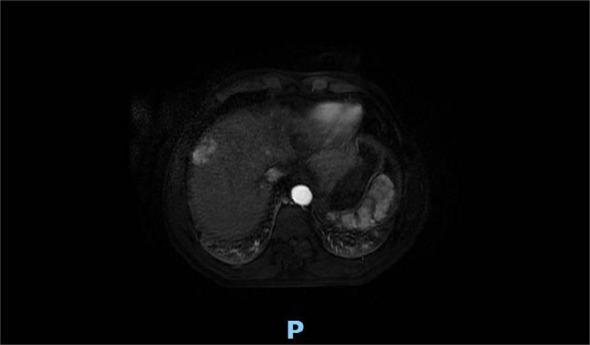

臀中肌转移的肝细胞癌治疗:1例病例报告及文献复习

Treatment of hepatocellular carcinoma with gluteus medius metastasis: a case report and a literature review.

Hepatocellular carcinoma (HCC) accounts for 85%-90% of all primary liver cancers (PLCs). Owing to the occult nature of HCC, most patients present at an advanced stage at the time of initial diagnosis and have a poor prognosis. With regard to systemic therapy, targeted therapy and immunotherapy are currently the centers of clinical research. With regard to local treatment, surgical resection, radiofrequency ablation, hepatic artery chemoembolization, and radiotherapy are commonly used. Interstitial brachytherapy is commonly used for the treatment of cervical and genitourinary cancers. In this case, interstitial brachytherapy was used to treat gluteus medius muscle metastasis from PLC, with good local control and symptom relief.

摘要

肝细胞癌(HCC)占所有原发性肝癌(PLC)的85%-90%。由于HCC具有隐匿性,大多数患者在初诊时已处于晚期,预后较差。在全身治疗方面,靶向治疗和免疫治疗是目前临床研究的重点。在局部治疗方面,手术切除、射频消融、肝动脉化疗栓塞和放射治疗是常用的方法。间质近距离放射治疗常用于治疗宫颈癌和泌尿生殖系统癌症。在本病例中,间质近距离放射治疗被用于治疗PLC的臀中肌转移,局部控制良好,症状得到缓解。